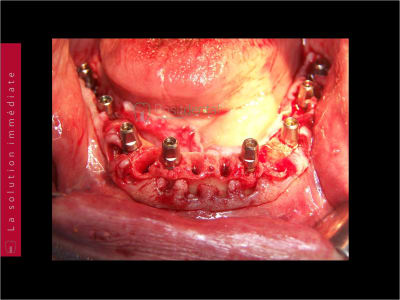

Le cas N°2 en images reelles :)

Guide métal avec support clavette, os assez fin : il est prévu un sticky bone complet : donc : lambeau avant extraction, positionnement du guide base et forage des clavettes, positionnement du guide implant, pose des piliers MU, controle des axes prothétique avec le guide pilier, collage des piliers prov sur le bridge a armature métal, occlusion nickel, sticky bone et PRF, sutures suspendues.